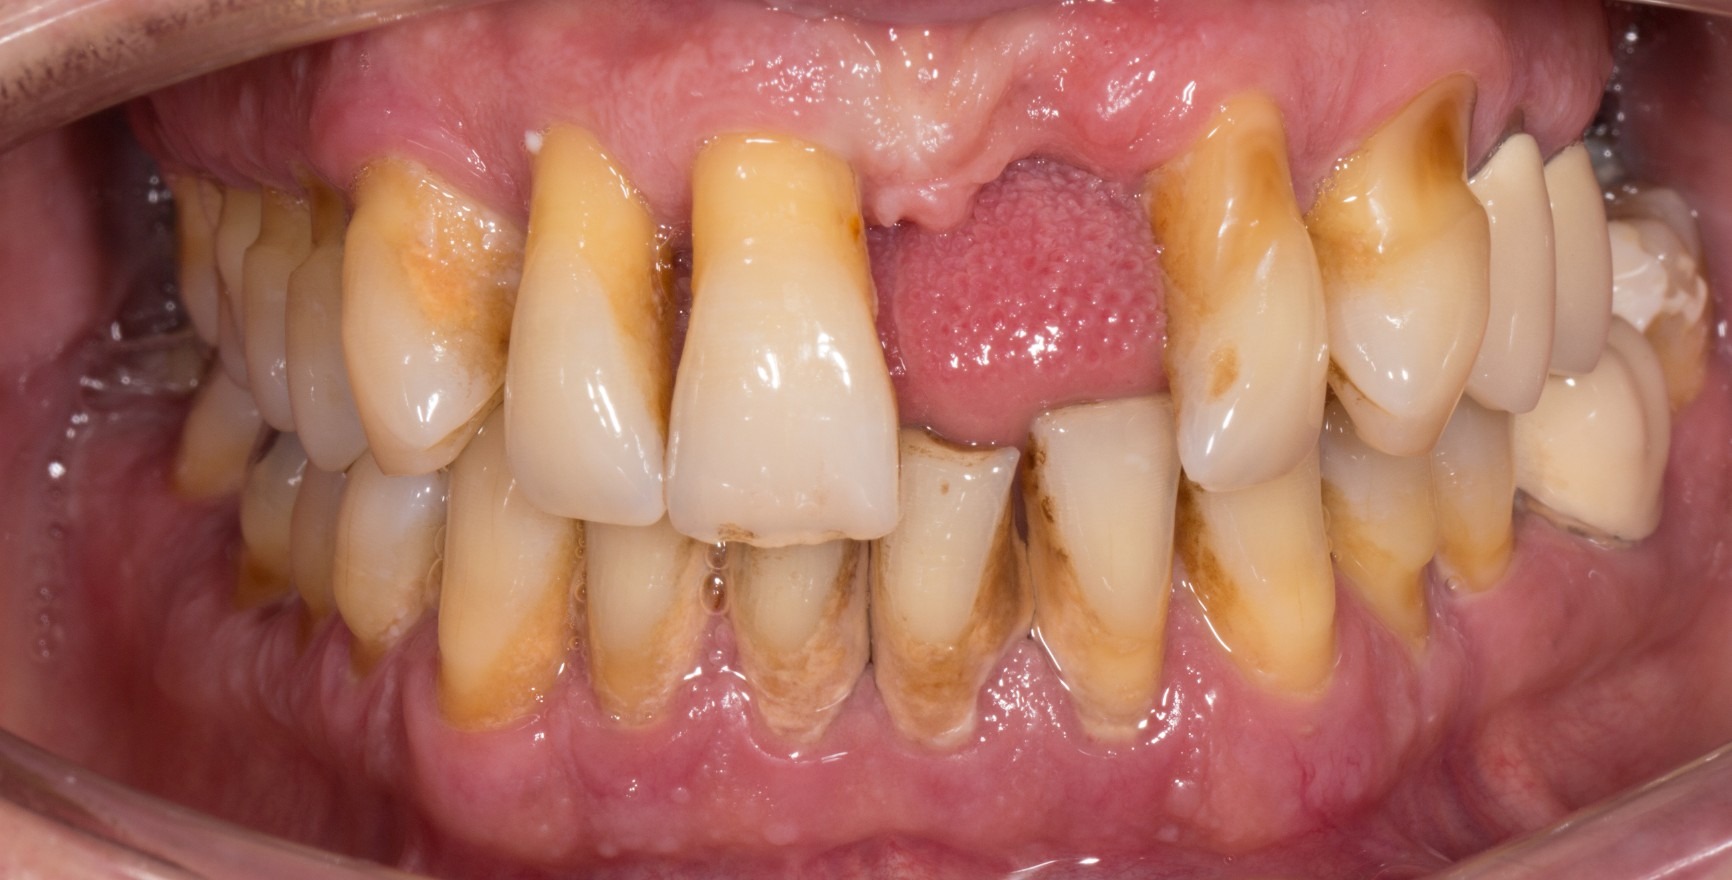

Новата класификация на пародонталните заболявания, представена през юни 2018 г., за първи път съдържа определение на понятието клинично пародонтално здраве (Lang & Bartold, 2018). Дори при оптимални хигиенни условия в гингивалния сулкус е налице малко количество бактериален биофилм. Пълното отсъствие на бактерии не е възможно в клинични условия. Хистологичният отговор представлява ограничен субепителен инфилтрат от неутрофилни гранулоцити (PMN). Въпреки това, при условие че се поддържа хомеостаза между биофилма и малкото количество PMN инфилтрат, това състояние се разглежда като израз на имунологичен контрол и следователно като физиологичен, а не патологичен (възпалителен) процес (Brecx et al., 1987a+b). Микробиологичното натоварване и факторите на гостоприемника определят дали състоянието на клинично пародонтално здраве ще се запази. Локално те могат да доведат до повишено натрупване на биофилм (напр. неподходящи зъбни възстановявания или неблагоприятни позиции на зъбите) или да повлияят на имунния отговор (напр. системни заболявания).

Състоянието на клинично пародонтално здраве на интактен пародонт се разграничава от това на редуциран пародонт, който вече е засегнат от клинична загуба на прикрепване. Тази загуба на прикрепване може да настъпи:

в резултат на възпаление в хода на пародонтита. Клиничното пародонтално здраве описва стабилното състояние след успешно приключване на пародонталното лечение.

Клиничният критерий винаги е липсата на кървене при внимателно сондиране (кървене при сондиране = BoP). Прави се разграничение между специфична за мястото/зъба диагноза с липса на BoP на съответното място на измерване и специфична за пациента диагноза, при която прагова стойност на BoP ≤ 10 % все още отговаря на критериите за клинично пародонтално здраве. Дълбочината на сондиране не трябва да надвишава 3 mm. При намален пародонт след пародонтално лечение прагова стойност от 4 mm все още се счита за стабилно състояние (Matuliene et al., 2008).